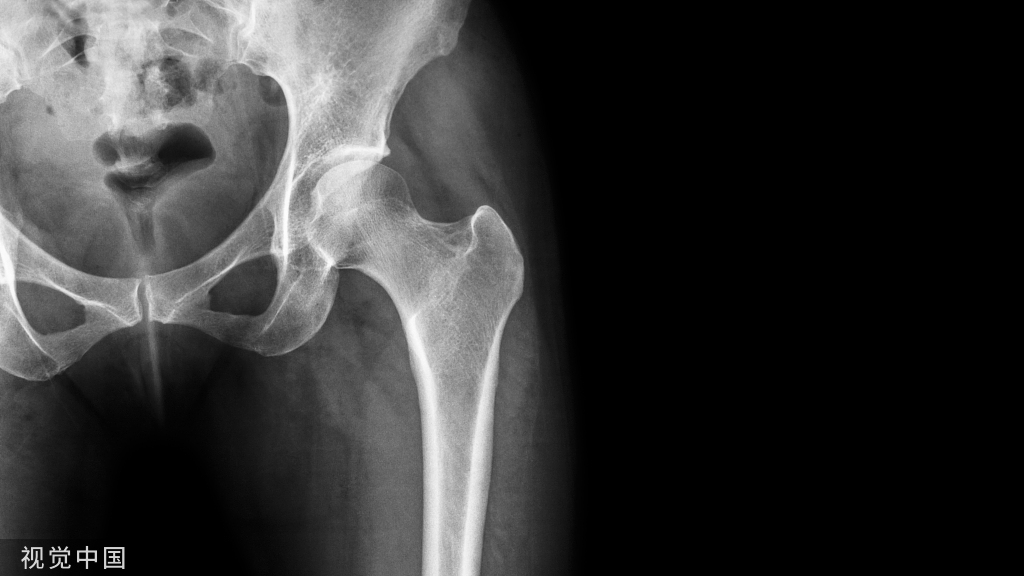

FAI手术技巧:严重骨量减少时外踝骨折的复位技术!